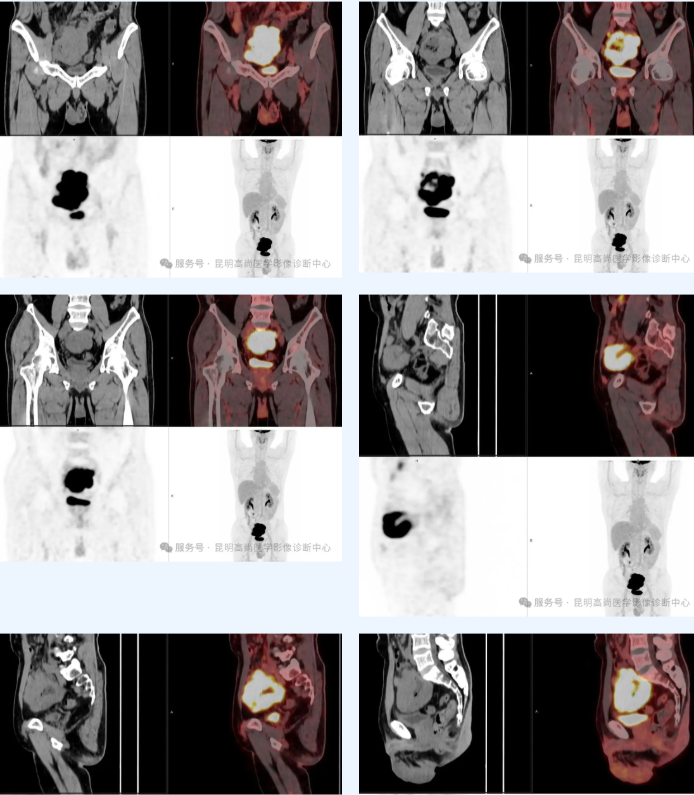

患者男性,51 岁;两个月前出现便血,外院胃肠镜:食道隆起病变,回盲部占位并狭窄;回盲部组织病检:恶性肿瘤,建议结合免疫组化;肿标 TSGF 偏高,要求 PET/CT 明确病变性质;既往右腕关节骨折史,痔疮手术史,否认外伤过敏史,否认传染病史。

盆腔内回肠巨大肿块并糖代谢明显增高,符合淋巴瘤;周围肠系膜多发淋巴结增大并糖代谢轻度增高,肿瘤浸润待排,建议随诊。

CT:肠管形态不规则,变形或者狭窄,肠壁增厚;肠腔外与肠腔内存在肿块,局部肠管动脉瘤样扩张;系膜与后腹膜淋巴结肿大;增强后多呈均匀轻中度强化;多边界清楚;肠壁具有一定的柔软度,梗阻和僵硬少见。

PET/CT:病变区域(如肠壁增厚处、肿块或受累淋巴结)通常会出现 FDG 摄取增高;治疗完成后,PET-CT 在检测残留或复发的淋巴瘤方面具有很高的敏感性,即使在早期阶段也能检测到。